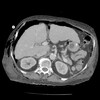

What pathology is seen here?

243

Hepatocellular Carcinoma (HPC)

What pathology is seen here? Label A-D

Hepatocellular Carcinoma (HPC) -Multiphase study A: Non contrast: Mass is hypodense B: Arterial phase: Aorta bright, tumour enhanced, non uniform enhancement (mish mash) C: Portal venous phase D: Delayed phase